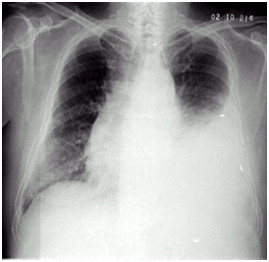

02卷-5.女性,55歲,胸悶、氣短5天,加重1天。診斷(本題滿分2.00分)

A.右上肺炎

B.左側(cè)胸腔積液

C.左下肺不張

D.左肺癌

本題答案:B

題目解析:

【該題針對“ X線-胸腔積液 ”知識點進(jìn)行考核】